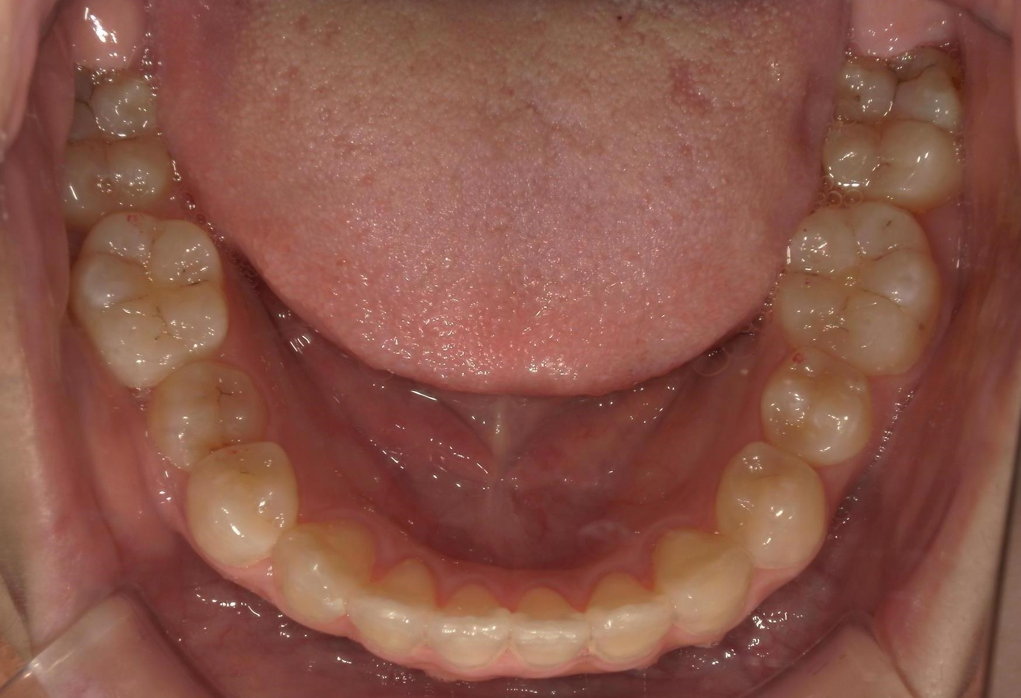

年齢 20代女性

主訴

上顎前突

前歯叢生

AFTER